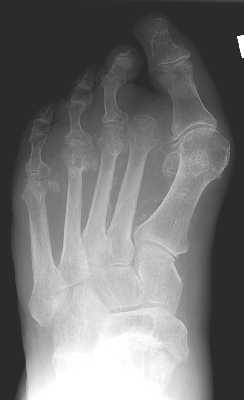

The above images show both the pre-operative and post-operative left foot of the same

patient. The pre-op film demonstrate osteomyelitis of the distal first phalanx that

was treated with a great toe amputation.